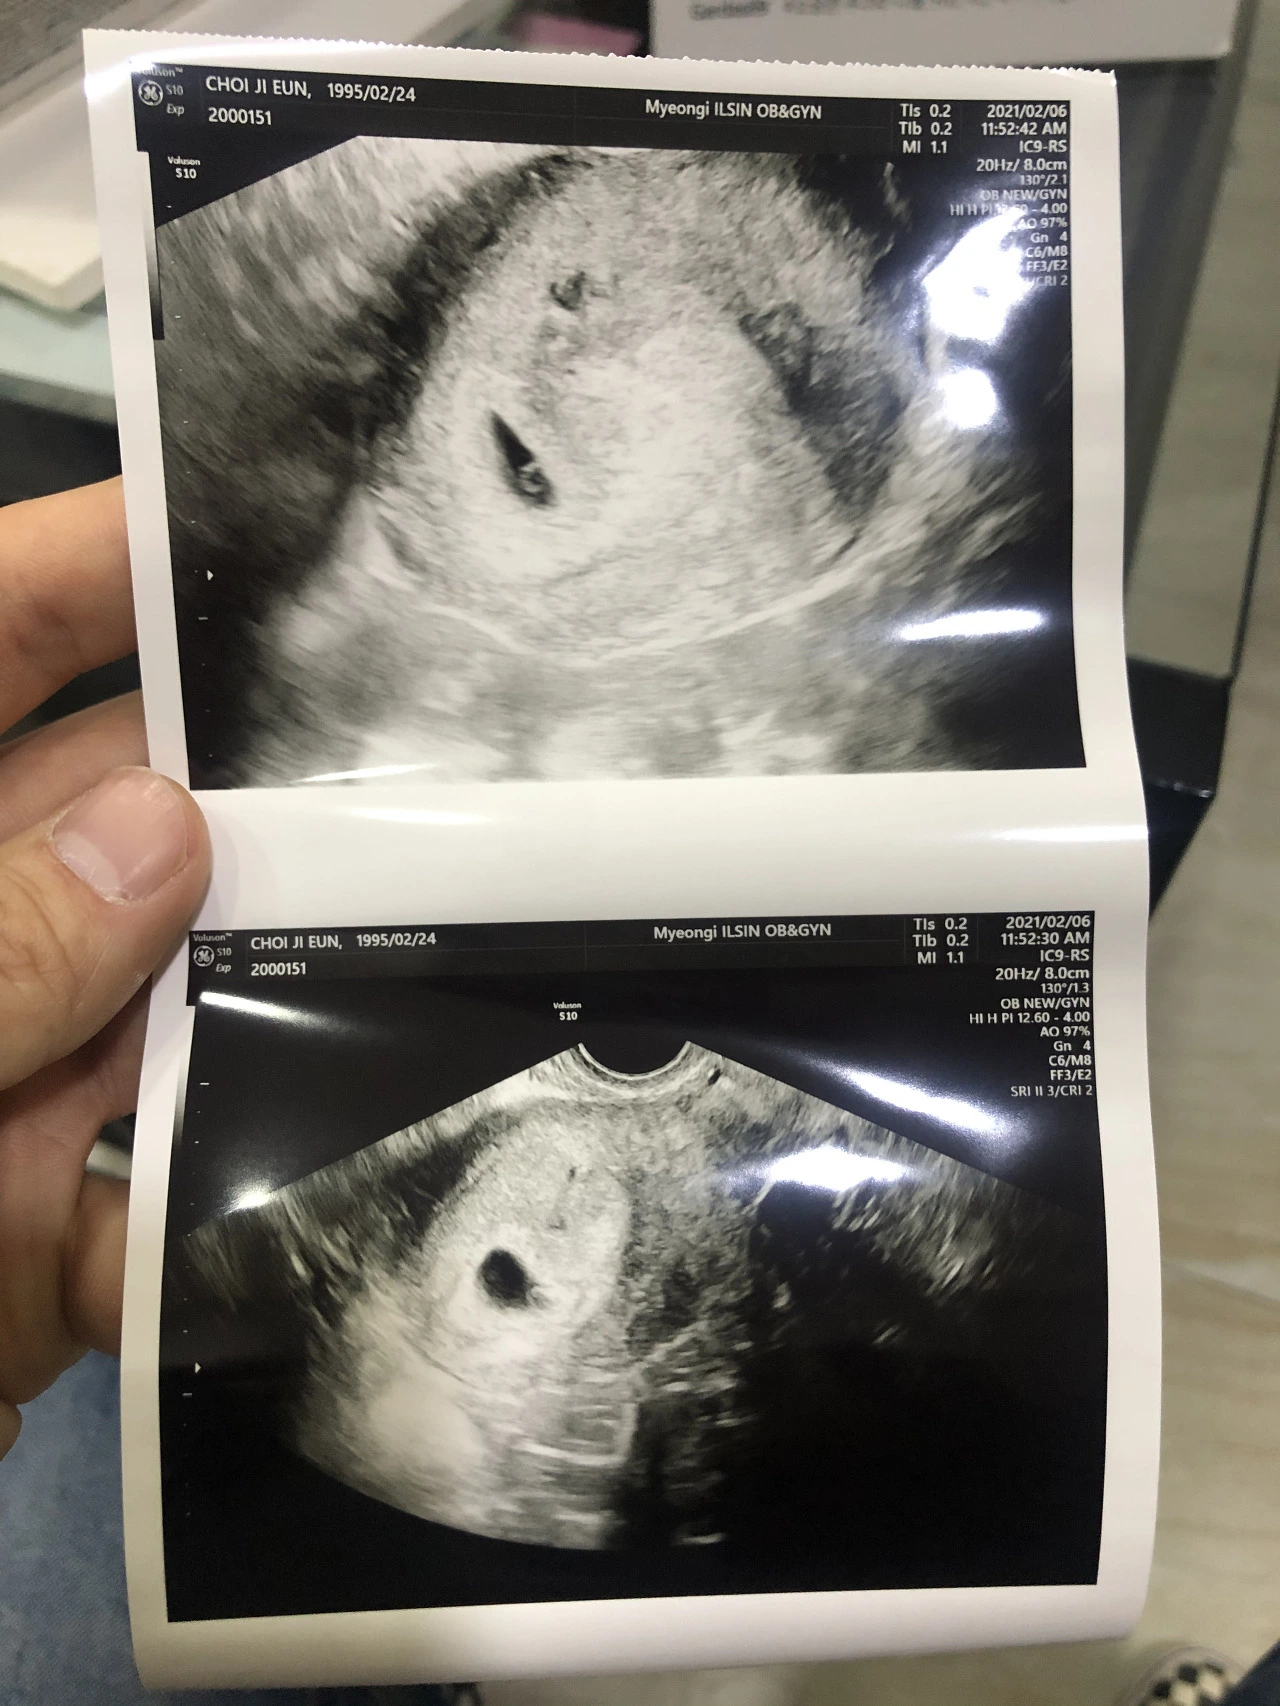

스크린샷 2022-10-17 오전 10.49.32.png 이랬던 네가 하나의 생명이 되어 태어나다니!